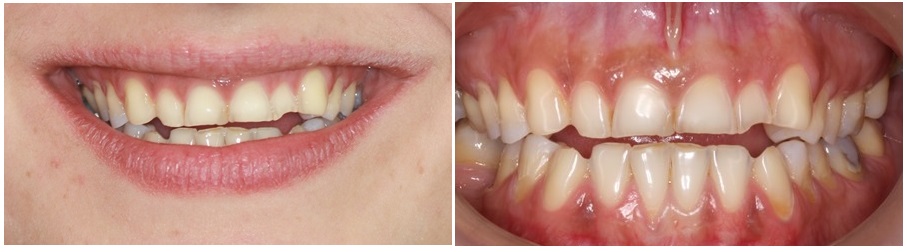

Βλέπετε στην φωτογραφία που ακολουθεί, εικόνα δοντιών με σημαντική διάβρωση που έχει προκληθεί από εμετούς. Στις εικόνες μπορούμε να παρατηρήσουμε τα χαρακτηριστικά της διάβρωσης, όπως το εντονότερο χρώμα των δοντιών στα σημεία όπου χάθηκε η αδαμαντίνη και την αλλαγή της μορφολογίας των δοντιών.

Η διάβρωση των δοντιών προκαλεί αλλαγές στα δόντια σταδιακά και τα αποτελέσματα χρειάζονται χρόνο γα να γίνουν αντιληπτά από τους ασθενείς. Οι αλλαγές εμφανίζονται αρχικά στα δόντια της άνω γνάθου και σε προχωρημένο βαθμό και στα δόντια της κάτω γνάθου.

- Αλλαγή της μορφολογίας των δοντιών. Τα δόντια χάνουν την ανατομικότητα τους, γίνονται πιο λεπτά και το κοπτικό άκρο των μπροστινών δοντιών γίνεται διαφανές και σπάει εύκολα.

- Αλλαγή του χρώματος των δοντιών. Η απώλεια της αδαμαντίνης από την διάβρωση, επιτρέπει στην πιο έντονα χρωματισμένη οδοντίνη που είναι το αμέσως επόμενο στρώμα κάτω από την αδαμαντίνη, να φαίνεται περισσότερο. Έτσι τα διαβρωμένα δόντια φαίνονται προοδευτικά πιο κίτρινα.